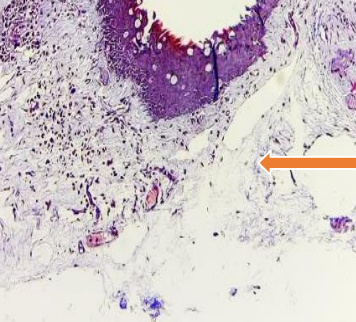

Mixed loose & dense connective tissue (arrow) stained with Massone Trichrome stain